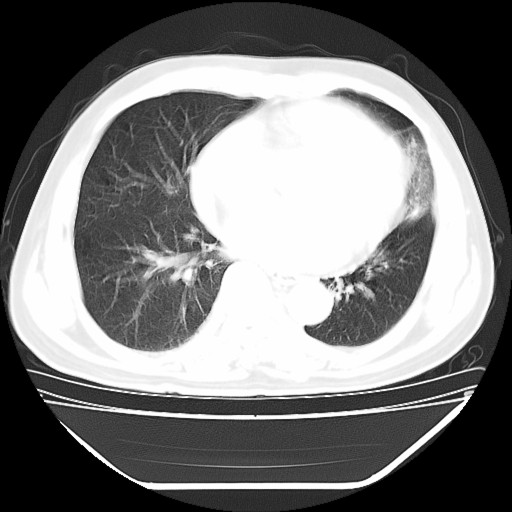

以下是引用hhcckk在2009-5-29 10:34:00的发言:[br]左下肺片絮状边缘模糊影,考虑感染,建议治疗后复查[br]